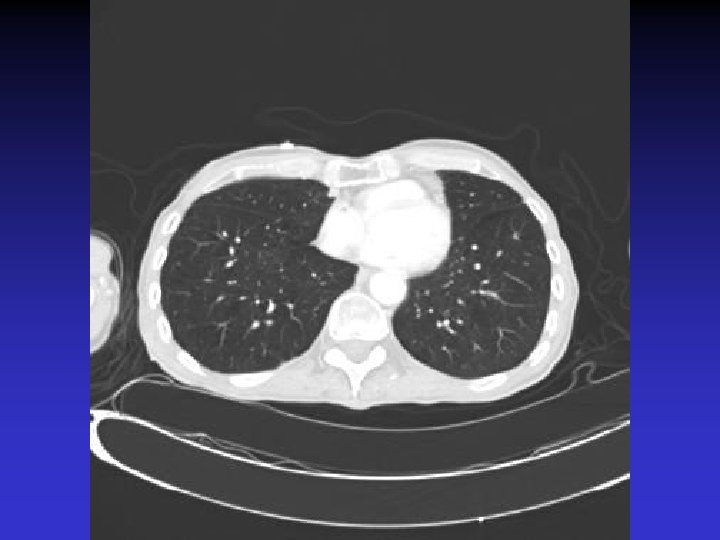

NTM lung disease n n MAC, M. kansasii, M. abscessus >50 years, ? M vs. F Symptoms n variable, nonspecific n chronic or reoccurring cough n sputum production, fatigue, malaise, dyspnea, fever, hemoptysis, chest pain, wt loss n more constitutional symptoms with advancing disease n evaluation complicated by sx of coexisting lung disease CXR n Fibrocavitary – often like MTB, but may be dense airspace dz or solitary cavity w/o cavitation n Nodular/bronchietatic – typical MAC, usu. mid-lower lung fields, +/- cavitation

M. simiae n n M. simiae may be confused with MTB as it is the only niacin-positive NTM Maoz et al. compared pts in Israel with M. simiae vs MTB. Pts with M. simiae: n More females, older age n Higher rates of smoking, COPD, other dz (DM, CAD, cancer), immunosuppressive drugs n Less HIV n Blunted symptoms n More noncavitary infiltrates in middle/lower lobes Most M. simiae isolates were contaminants Treatment with clarithromycin, ethambutol, rifabutin, and streptomycin (with modification for sensitivities)